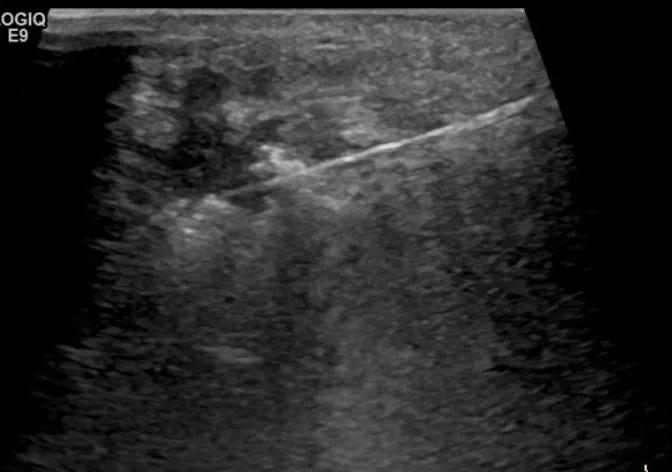

第三例是甲状腺癌患者,双侧甲状腺癌切除术后、碘治疗后一年余效果欠佳,超声显示左颈3区3枚低回声结节,穿刺示甲状腺乳头状癌转移。患者不愿意手术,希望采取局部治疗。对病灶进行液体隔离后采取热消融术,由于淋巴结较小,热消融一分钟左右完全灭活,术后增强影像显示没有脏器充填。

(病例3图例)